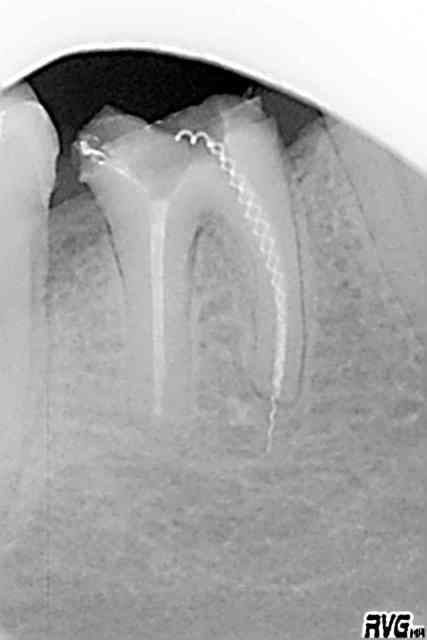

un patient vient consuulter pour une desmodontite

apres cavité d'acces et nogociation des canaux aux limes manuelles, les canaux ont été preparés avec le CMA, soudain, ploc, un bout de la lime NiTi est resté coincé dans le canal, 1/3 median

j'ai essayé deseperement de faire ( passing by ) et hop ça passe, mais, le fait de le retirer n'a pas été possible..svp vos conseils....